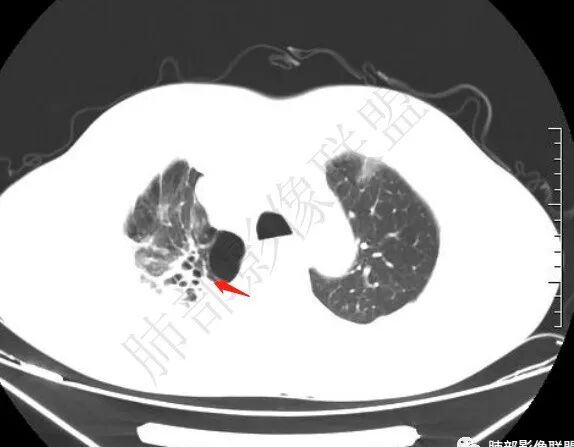

晨读:右肺上叶胸膜下实变影伴有肺大泡(结核?),前纵隔一实性肿块,骑跨主动脉生长,病变侵犯压迫腔静脉,平扫密度均匀,增强扫描均匀强化,内部可见低密度小坏死区无强化,考虑:淋巴瘤,鉴别胸腺癌(坏死偏少)

晨读:男,60岁,颜面部肿胀1月入院。CT示右肺上叶条索影及实变影伴局部支气管扩张,肺大泡(陈旧性肺结核?)。前纵隔可见实性肿块,骑跨主动脉生长,平扫密度不均匀,内部可见低密度区,增强扫描渐进性不均匀强化,可见坏死区,上腔静脉受侵,考虑为恶性,侵袭性胸腺瘤或胸腺癌>淋巴瘤

▲右上叶、下叶胸膜下为主的斑片实变影,局部结构变形。支气管后移。支持慢性炎性病变,结核可能。从这个角度分析:纵隔肿瘤与肺部病灶关系不密切。